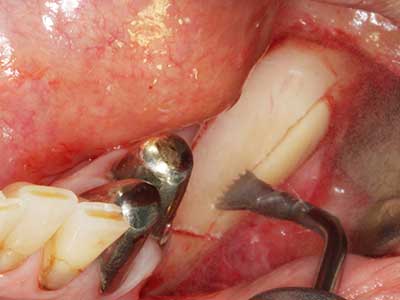

Abb. 18: Präparation eines Kortikalis-Deckels mit der Piezo-Knochensäge (Piezomed, W&H).

Abb. 19: Operationssitus nach Neurolyse und Osteomentfernung.